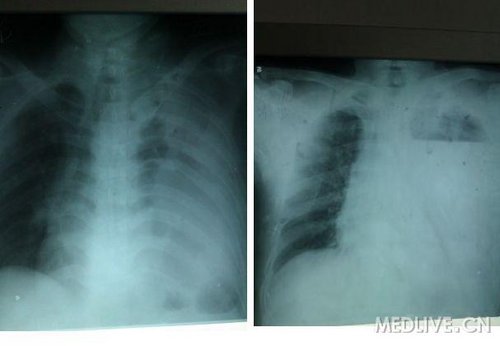

拔管后第二天 患者于变动体位后出现左侧胸痛,伴气促,急查心电图无异常,D 2聚体0.7mg/l,双侧呼吸音尚清晰,无干湿啰音,内科会诊考虑肺栓塞不除外,建议给予抗凝治疗,拔管后第三天 仍诉气促及胸痛不缓解,听诊左肺呼吸音消失。急查胸片:

于局麻下胸穿 为血性液体60ML b超定位 肩胛下传出黄色液体15ml 无异味 。于原闭式引流位置再次置管。